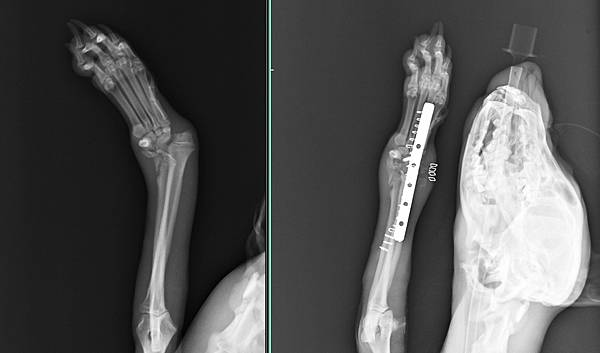

經過醫療團退努力後

很快又恢復調皮走跳的本性

手術後兩天